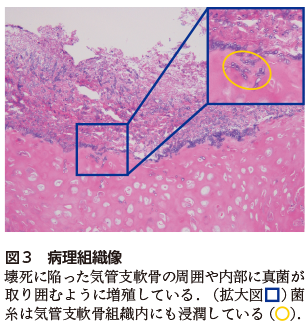

本症例では,胸部CTにおいて散在性に結節影を認め,多くは内部に三日月状の透亮像を伴っていた(図2).血液検査ではβ-Dグルカン141.9 pg/mL,アスペルギルス抗原4.7(陽性)であり,IPAを疑い気管支鏡検査を施行した.気管支洗浄液培養でAspergillus fumigatusが同定され,病理組織学的には壊死に陥った気管支軟骨の周囲や内部に真菌が取り囲むように増殖している所見を認めた(図3).以上よりIPAと診断した.

IPAの胸部CT所見としては,結節影,浸潤影,楔状陰影を呈することが多い.発症早期には血管侵襲に伴う周囲出血を反映し,結節周囲にすりガラス影(halo sign)を伴うことがある.病勢の進行により壊死巣が空洞化し,あるいは血球減少患者の好中球回復期には,空洞内に三日月状透亮像(air-crescent sign)が出現することが知られている1).本症例ではair-crescent signを伴う多発結節影を呈し,好中球回復期のIPAとして合致するCT所見であった.さらに病理学的にもアスペルギルスの組織浸潤が観察された.

図2